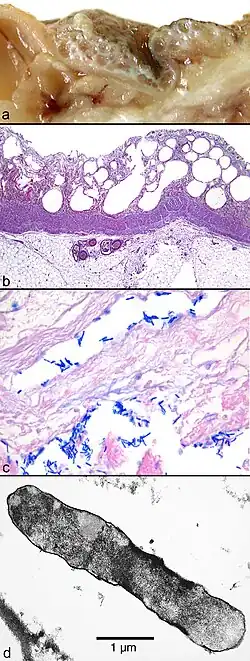

Га́зовая гангре́на (или анаэробная гангрена, мионекроз) — вид гангрены, представляющий собой омертвение тканей организма, вызванное инфекцией, обусловленной ростом и размножением в тканях клостридиальной микрофлоры. Рост этой микрофлоры возможен только при отсутствии кислорода (анаэробно), однако споры возбудителей заболевания могут длительное время сохраняться и в кислородной среде (на воздухе).

Заболевание вызывается преимущественно бактериями рода клостридий, которые обитают в почве и уличной пыли[3]. Раны, загрязнённые землёй, имеющие раневые карманы, участки омертвевшей либо плохо снабжаемой кровью ткани, не подвергшиеся первичной хирургической обработке, предрасположены к газовой гангрене. В подходящих условиях возбудитель размножается быстро, выделяя тканерастворяющие и газообразующие экзотоксины, которые способствуют ещё более быстрому распространению инфекции.

Диагноз ставится на основании характерной раны, общей интоксикации. Диагноз подтверждается рентгенологически (определяется «пористость» мышечных тканей) и микроскопически (обнаружение клостридий в раневом отделяемом). Дифференциальный диагноз проводят с фасциальной газообразующей флегмоной (нет поражения мышц) и путридной (гнилостной) инфекцией.